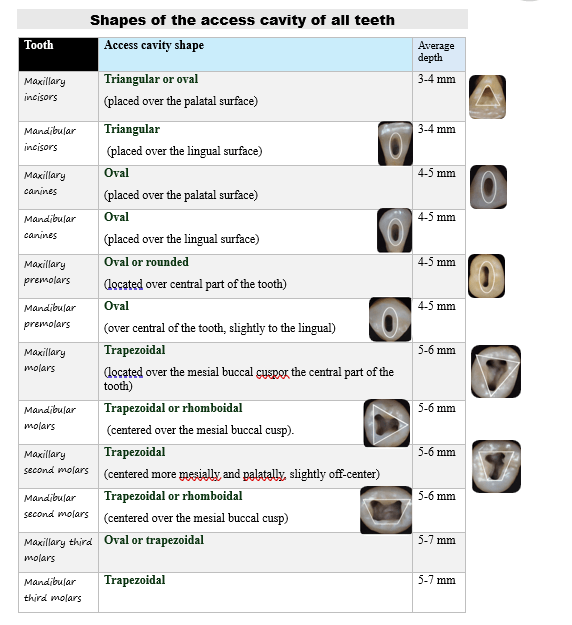

Shapes of the access cavity of all teeth

| Tooth | Access cavity shape | Average depth |

|---|---|---|

| Maxillary incisors | Triangular or oval (placed over the palatal surface) |

3-4 mm |

| Mandibular incisors | Triangular (placed over the lingual surface)

|

3-4 mm |

| Maxillary canines | Oval (placed over the palatal surface)

|

4-5 mm |

| Mandibular canines | Oval (placed over the lingual surface)

|

4-5 mm |

| Maxillary premolars | Oval or rounded (located over central part of the tooth)

|

4-5 mm |

| Mandibular premolars | Oval (over central of the tooth, slightly to the lingual)

|

4-5 mm |

| Maxillary molars | Trapezoidal (located over the mesial buccal cusp or the central part of the tooth)

|

5-6 mm |

| Mandibular molars | Trapezoidal or rhomboidal (centered over the mesial buccal cusp)

|

5-6 mm |

| Maxillary second molars | Trapezoidal (centered more mesially and palatally, slightly off-center) | 5-6 mm |

| Mandibular second molars | Trapezoidal or rhomboidal (centered over the mesial buccal cusp) | 5-6 mm |

| Maxillary third molars | Oval or trapezoidal | 5-7 mm |

| Mandibular third molars | Trapezoidal | 5-7 mm |